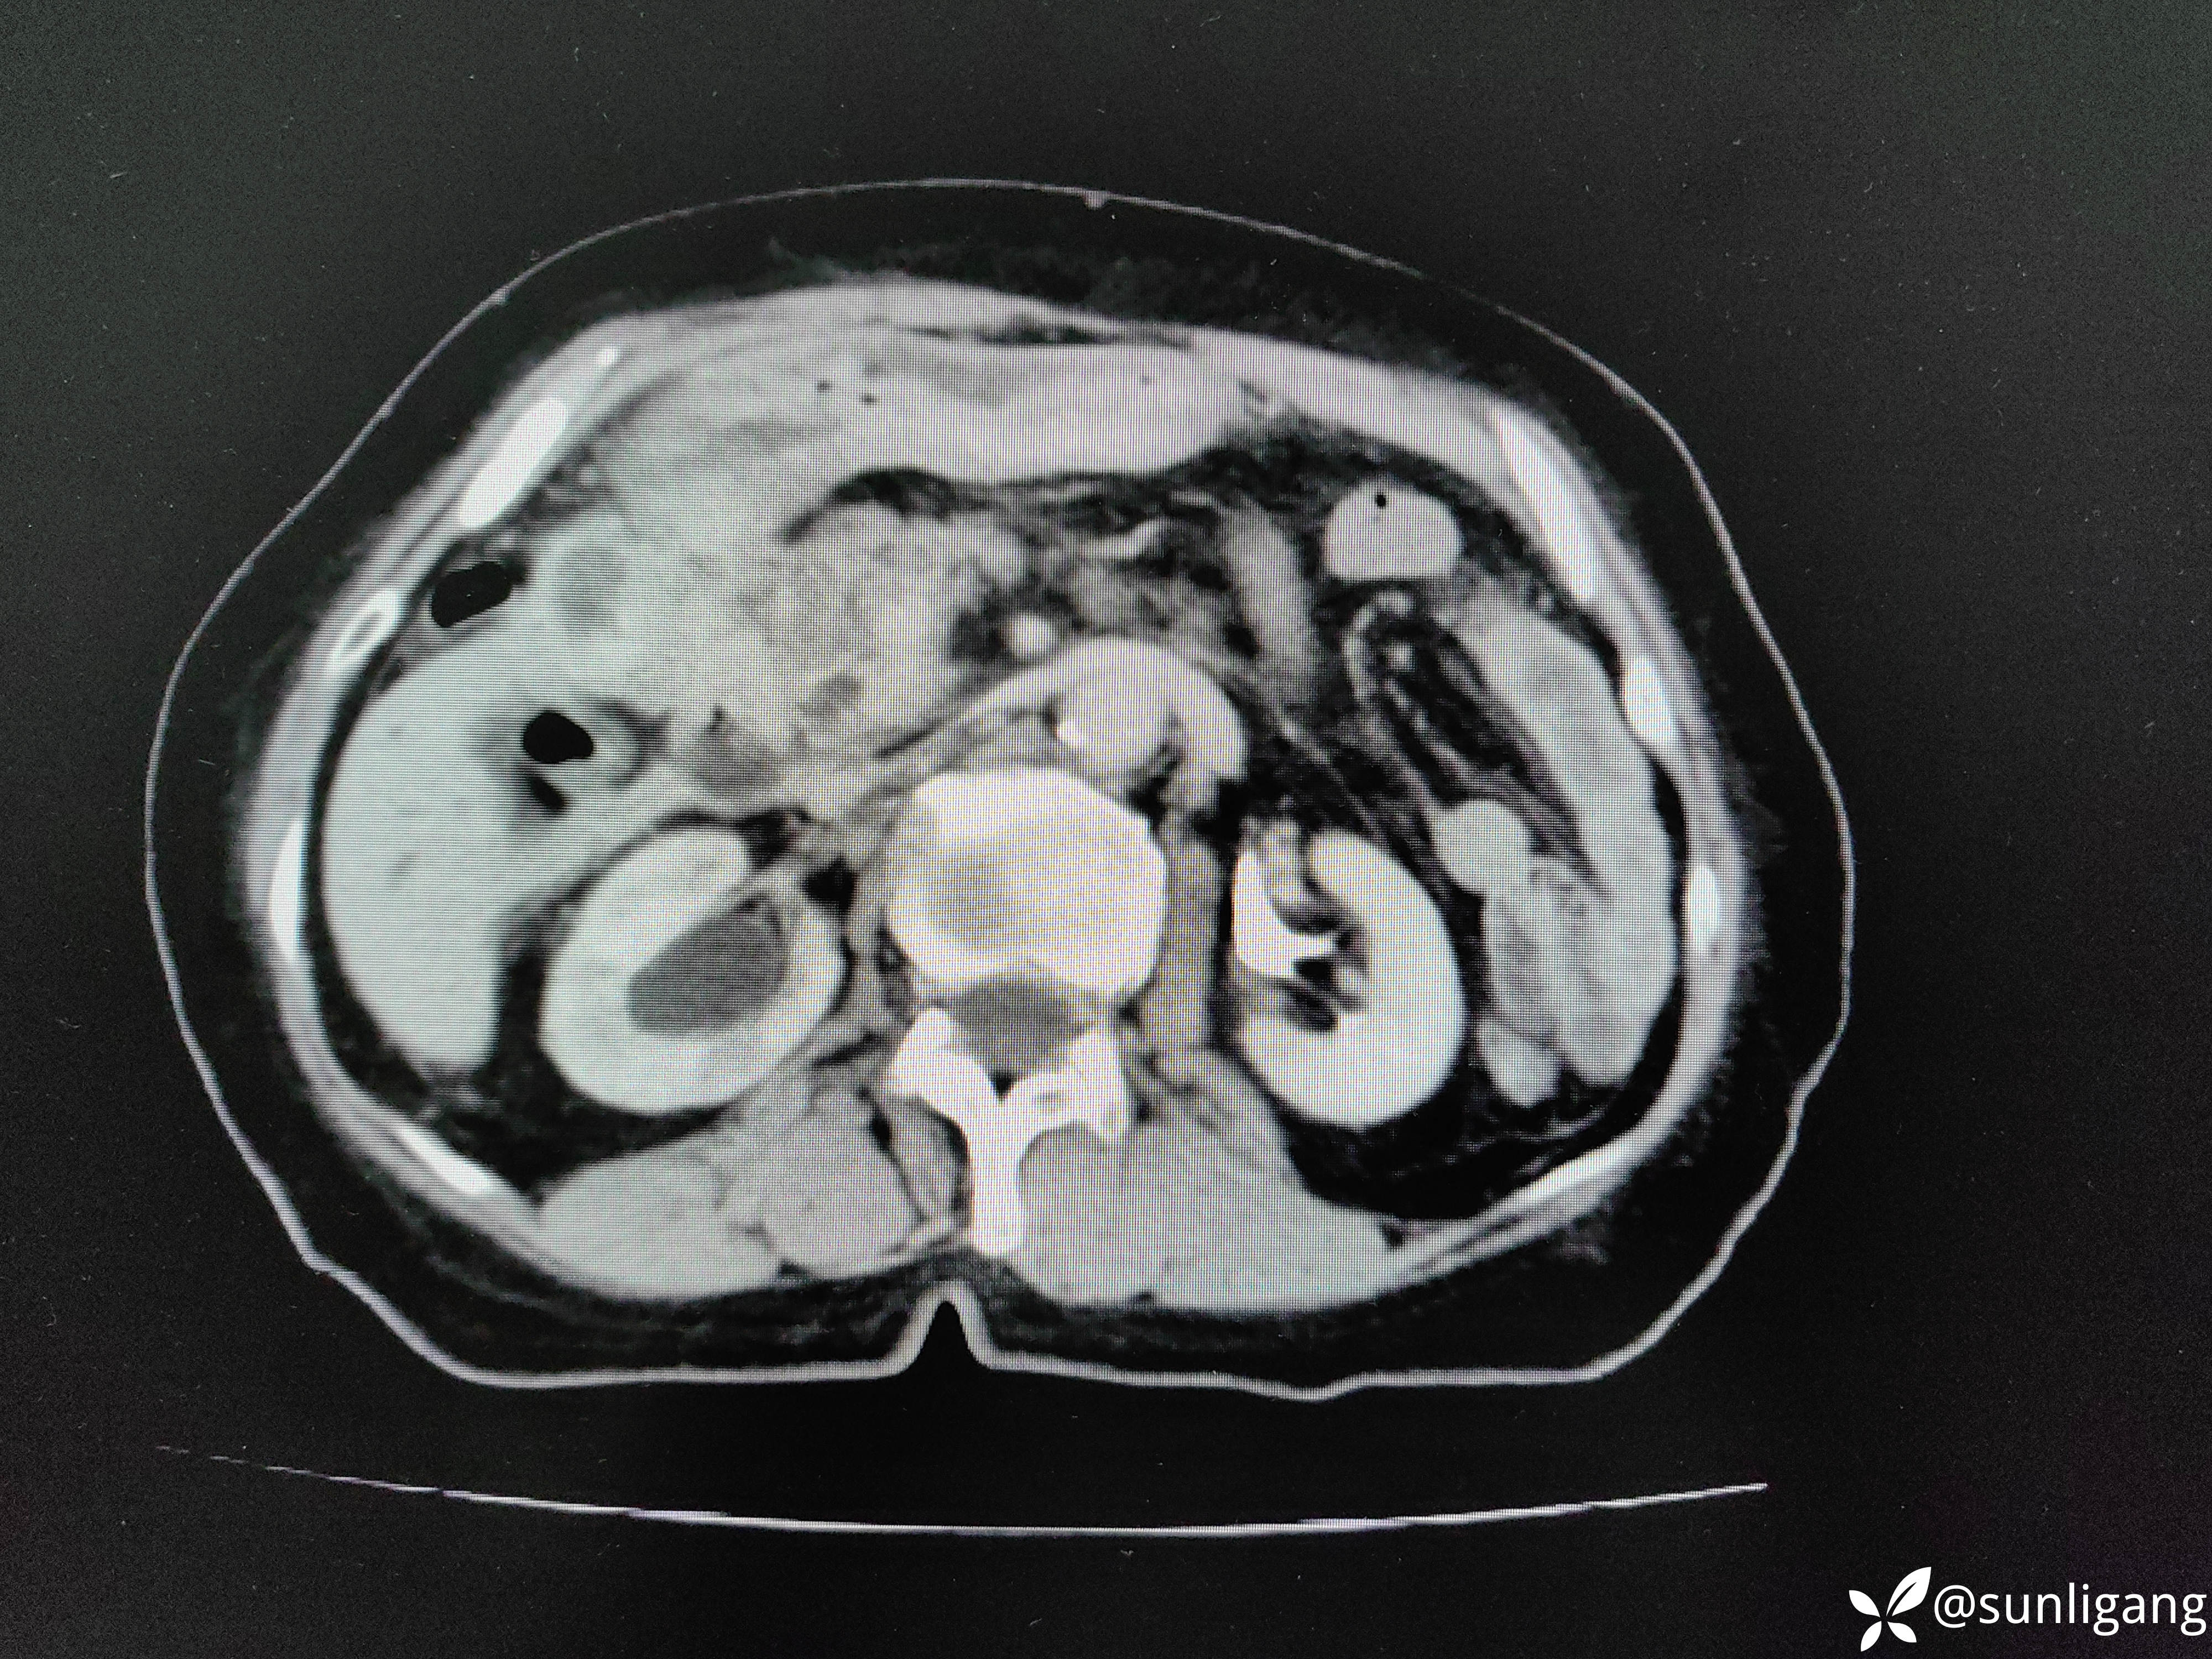

腹部CT平扫示:

上腹部平扫+增强CT如下图:

左右肝管都有明显扩张

胆囊周围靠近肝脏一侧有明显的不均质低密度影